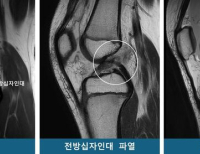

- 봉합 불가능한 회전근개 파열, 수술법에 따라 효과·합병증 위험 크게 달라

- 경기도에 거주하는 김 모씨(69세)는 수년 전부터 지속된 어깨통증으로 일상생활에 큰 불편을 겪었다. 팔을 들어 올리거나 뒤로 돌릴 때마다 심한 통증을 호소...

- 2025-09-19